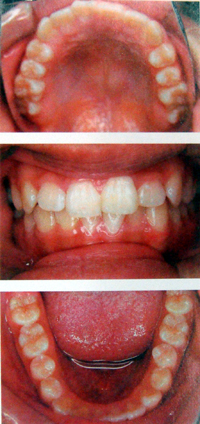

顎矯正(拡大矯正)SH療法は、1日10時間装置をはめて、あごを成長させる矯正です。お子様も大人も矯正することができます。

子供の場合・1日10時間装着

空間を広げ呼吸を楽にします。